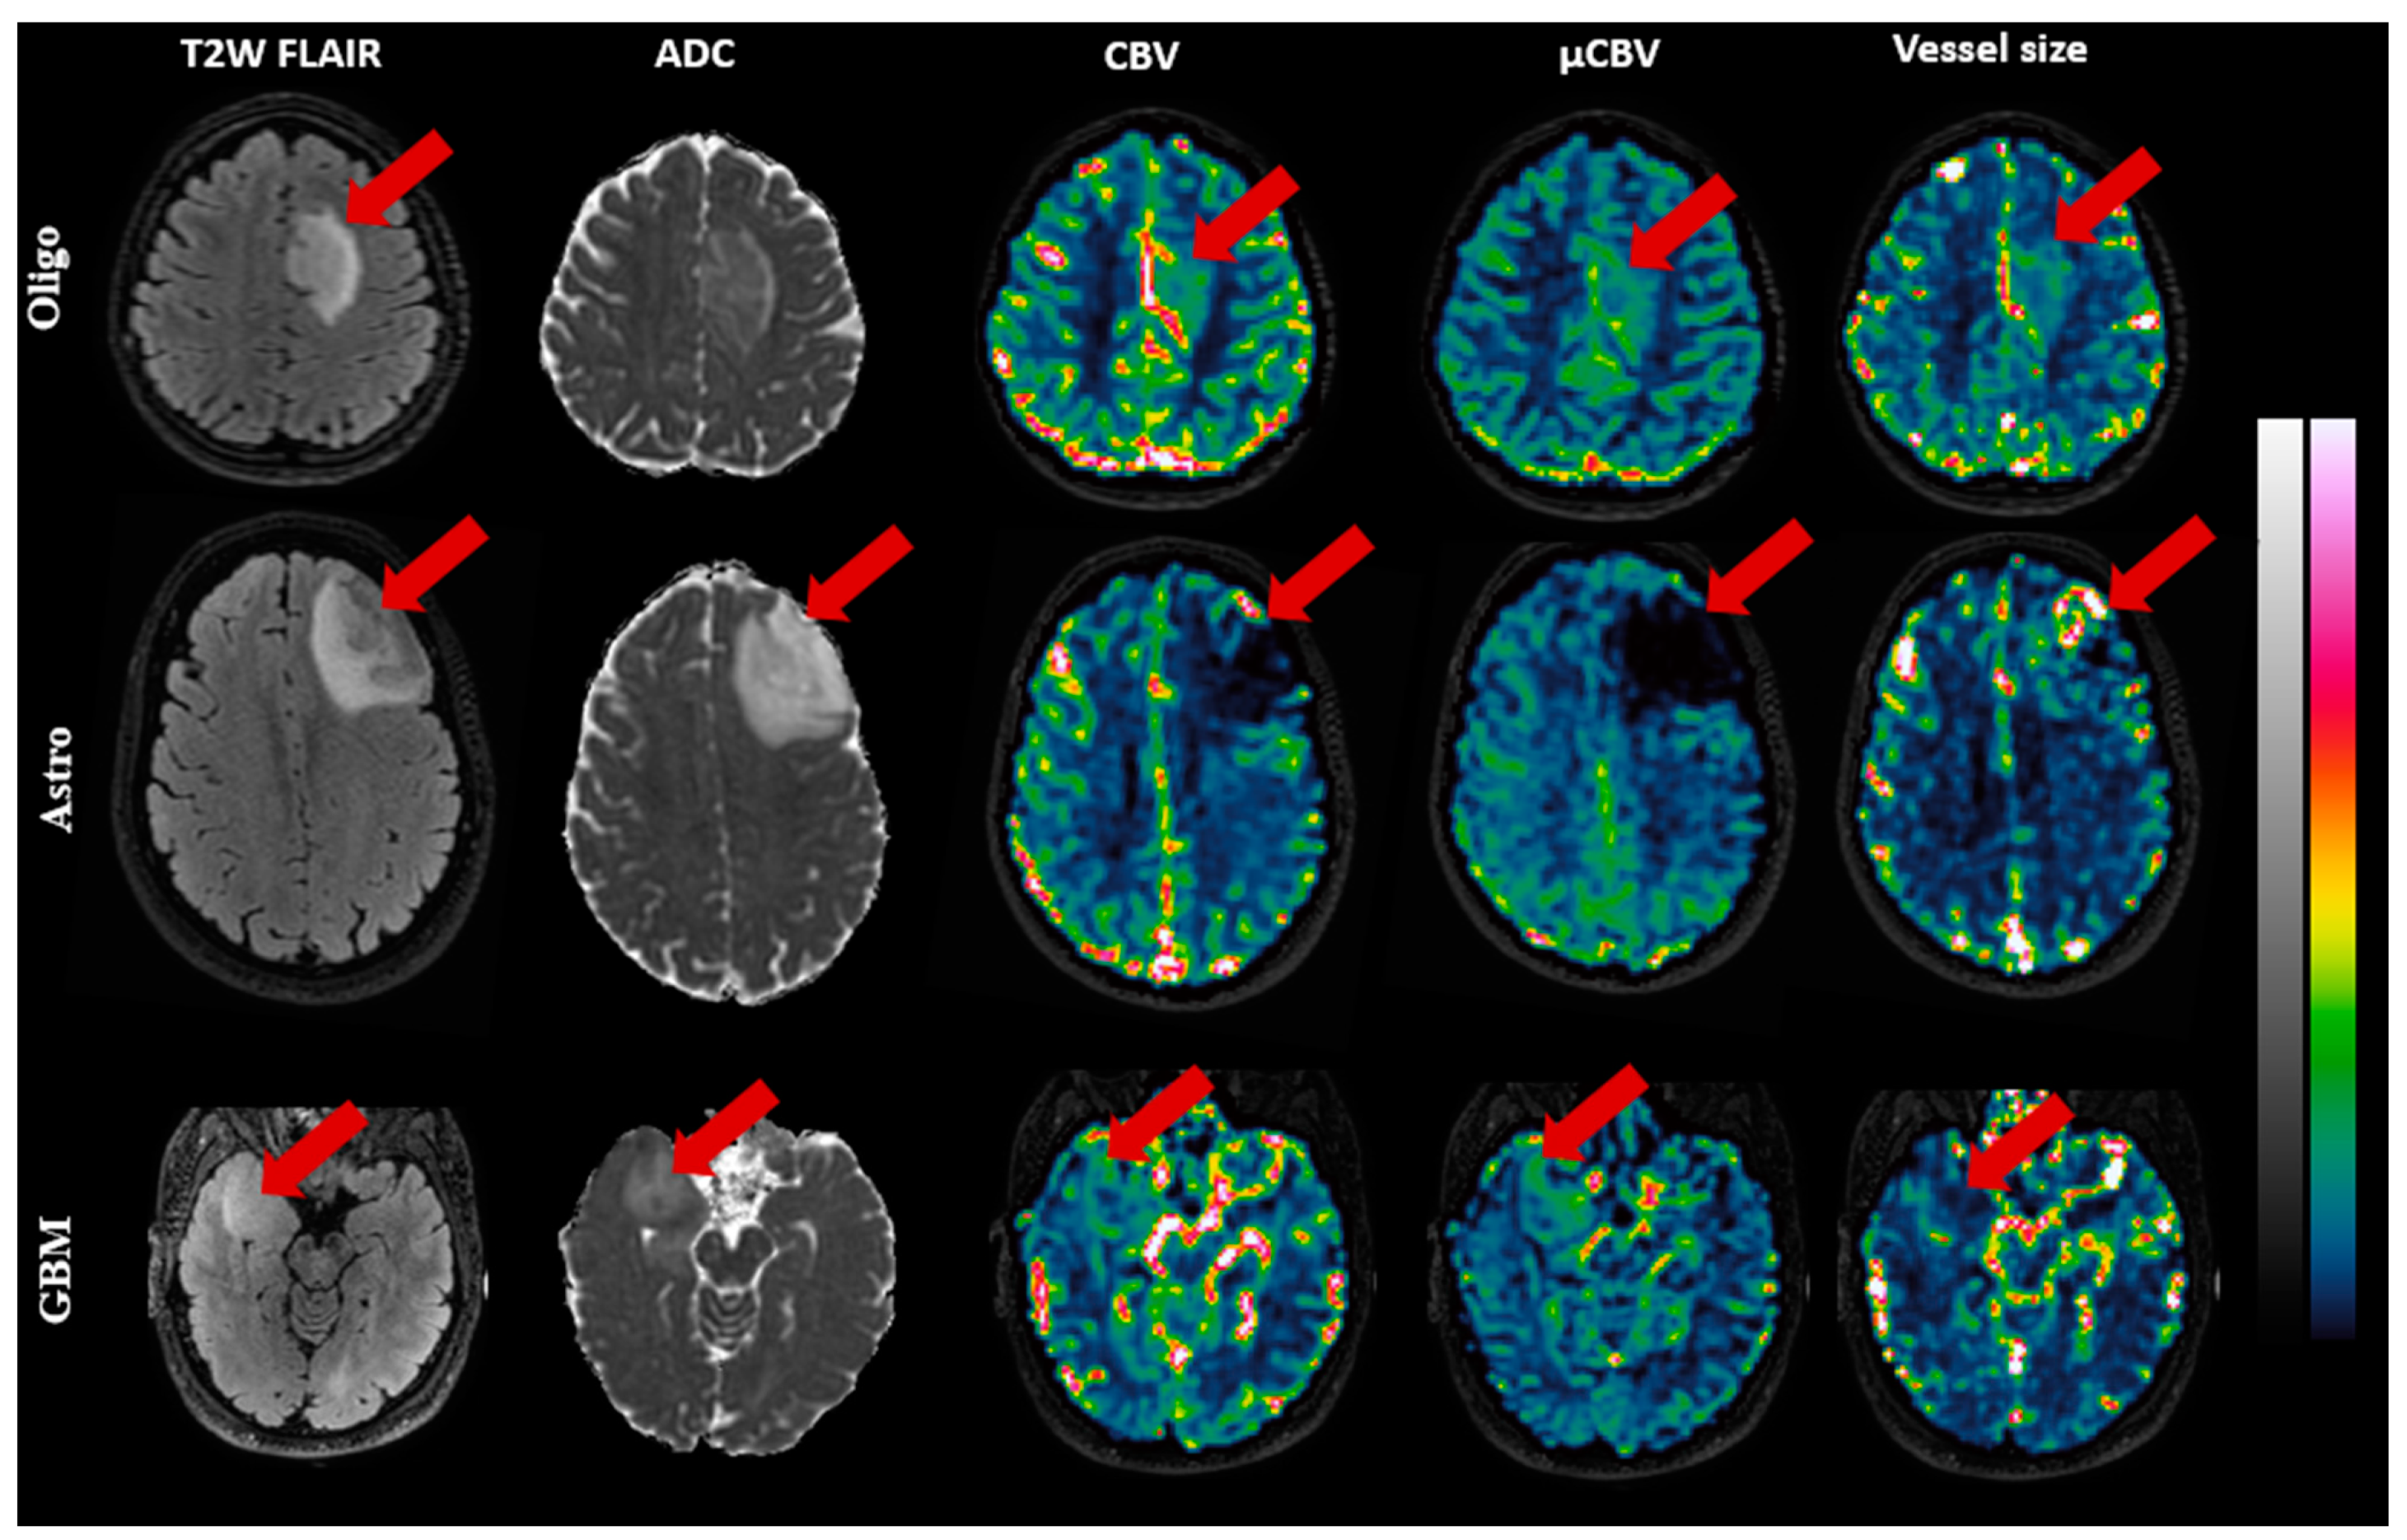

Figure 3 illustrates exemplary slices of CBV, µCBV, and vessel size maps for a representative patient of each subtype. In Oligo (IDH-mut&1p/19q-codeleted) and GBM (IDH-wt), both CBV and µCBV are distinctly high in the tumor area, while vessel size maps show low-to-intermediate intensity in the tumor area. In Astro (IDH-mut), the reverse is seen: CBV and µCBV are evidently low in the tumor area, while the vessel size map displays several hot spots in the tumor area.

Figure 3. Exemplary MR images of three patients, Oligo (IDH-mut &1p/19q co-deleted), Astro (IDH-mut), and GBM (IDH-wt), respectively, from top to bottom. The images (with color bars on the right) from left to right, respectively, are: T2W-FLAIR, ADC (0–1 µm2/s), CBV(0–10%), µCBV(0–10%), and vessel size (0–100 µm), with the red arrow pointing to the tumor.